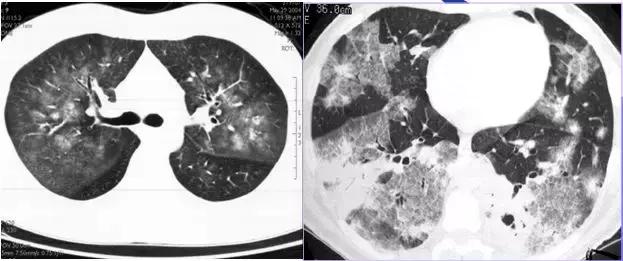

CT征象七:马赛克灌注

马赛克灌注(Mosaicperfusion)

在HRCT上,由于气道疾病或肺血管性疾病引起相邻的肺区血液灌注上的差别而出现的不均匀肺密度区,称马赛克/镶嵌性灌注。常见于造成局部气体滞留或肺实质通气不良疾病中 。

HRCT示略高密度磨玻璃密度影和低密度马赛克灌注区

由于气体储留引起的马赛克灌注

小气道病变引起两侧肺的马赛克灌注

小气道病变引起两侧肺的气体潴留